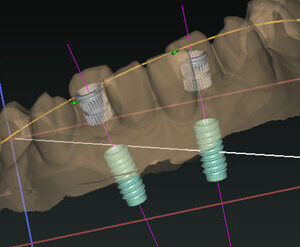

BTI Implant

Implant & công nghệ PRGF